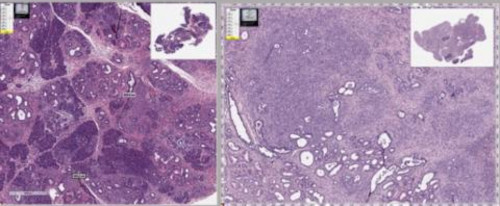

Ainsi une tumeur du pancréas chez la souris (coupe de gauche sur visuel ci-dessous) est pratiquement éliminée (visuel de droite) lorsque la souris est traitée avec un agent inflammatoire et le mébendazole. Une option à regarder de plus près alors que le cancer du pancréas est l’une des tumeurs malignes les plus agressives, avec une survie médiane globale qui reste inférieure à 5 mois. En cause son diagnostic le plus souvent tardif, un manque de médicaments efficaces et le développement, dans de nombreux cas d’une résistance au traitement. Le cancer du pancréas est ainsi le 3ème cancer le plus mortel dans les pays riches.

Le mébendazole pourrait jouer un rôle à tous les stades de la tumeur

L’équipe de la John Hopkins montre ici que l’antiparasitaire prévient l’initiation, la progression et les métastases du cancer du pancréas chez des souris génétiquement modifiées pour développer ce type de tumeurs. Les chercheurs utilisent 2 modèles de souris différents pour déterminer que le mébendazole peut ralentir ou arrêter la croissance et la propagation du cancer du pancréas à un stade précoce et/ou avancé.

L’étude préclinique : lorsque les chercheurs administrent du mébendazole à des souris modèles de cancer du pancréas, évaluent l’inflammation et observent les changements dans les tissus, le stade, le grade et l’état métastatique de chaque tumeur, ils constatent toute l’efficacité du médicament.